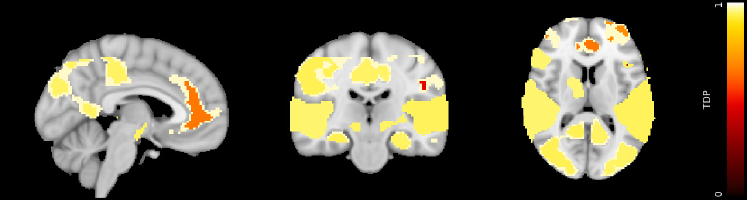

Results for the analysis of Section 10.2 are shown in Table 5, which contains the lower confidence bound for the TDP of each cluster, as well as the size and the coordinates of the maximum t-statistic. Figure 8 contains the map of the TDP lower confidence bounds obtained from the βquickβ setting. Results indicate that the setting of the βlongβ analysis does not provide larger TDP values than the βquickβ. While in this particular case βquickβ calculation settings tend to give slightly better results, the difference is dominated by the variability due to the random permutations.

| cluster | threshold | size | TDP () | coordinates | |||

| () | |||||||

| quick | long | ||||||

| FP/CG/SFG/TOF/LO/LG/ | 3.2 | -30 | -34 | -16 | |||

| OFG/ITG/SG/AG/NA | |||||||

| Left LO/TOF | 4 | -30 | -34 | -16 | |||

| Right LO/LG/ITG | 4 | 28 | -30 | -18 | |||

| Left SFG/FP | 4 | -28 | 34 | 42 | |||

| CG | 4 | 6 | 40 | -2 | |||

| Right FP | 4 | 30 | 56 | 28 | |||

| Left SG/AG | 4 | -50 | -56 | 36 | |||

| Right STG/PT/MTG/ | 3.2 | 60 | -10 | 0 | |||

| HG/PrG/T | |||||||

| STG/PT/MTG/HG | 4 | 60 | -10 | 0 | |||

| PrG | 4 | 52 | 0 | 48 | |||

| Left STG/PT/MTG/ | 3.2 | -60 | -12 | 2 | |||

| HG/IFG/T | |||||||

| HG/PT/MTG/STG | 4 | -60 | -12 | 2 | |||

| IFG | 4 | -40 | 14 | 26 | |||